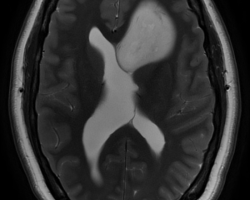

- IRM : coupes axiales, séquences en diffusion B1000, perfusion, T1 et T2 : tumeur hypoT1, hyperT2, peu de diffusion = peu d’œdème, localisation plutôt frontale. Pas de prise de contraste (pas de cliché ici = à compléter) Compte tenu de l’âge, évocateur d’un gliome bas grade. De ce fait, rechercher une comitialité avant tout geste chirurgical.

IRM : lésion basifrontale gauche développée aux dépens du gyrus rectus qui remonte vers l’hypothalamus comprimant les foramens de Monro induisant une probable hydrocéphalie obstructive. Pas de prise de contraste mais séquences en perfusion non exploitables.